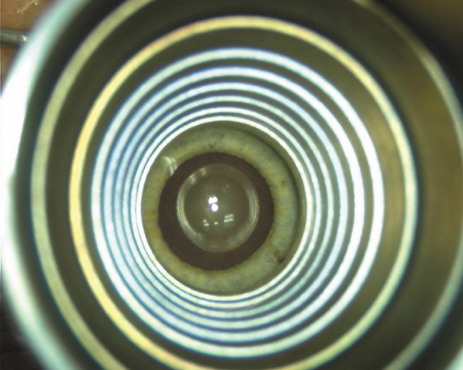

Proper centration of the incisions over the steep corneal meridian is of utmost importance. Increasing evidence supports the notion that significant cyclotorsion may occur when assuming a supine position.32 As previously noted, an axis deviation of only 15 degrees may result in a 50% reduction of surgical effect.5 For this reason, most surgeons advocate placing an orientation mark at the 12:00 or 6:00 limbus while the patient is in an upright position. This is particularly important when employing injection anesthesia wherein unpredictable ocular rotation may occur. An additional measure that may be employed to help center the relaxing incisions is to identify the steep meridian (plus cylinder axis) intraoperatively using some form of keratoscopy. The steep meridian over which the incisions are to be placed corresponds to the shorter axis of the reflected corneal mire. A simple handheld device such as the Maloney (Storz, Katena) or Nichamin (Mastel Precision) keratoscope works well, or a more robust and well-defined mire may be obtained through an elaborate microscope-mounted instrument such as the Mastel Ring of Light (Mastel Precision). Another common way in which the steep meridian is marked utilizes a Mendez Ring or similar degree gauge that is aligned with the previously placed limbal orientation mark, and the cylinder axis is then located on the 360-degree gauge.